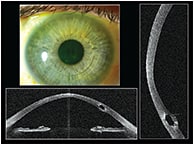

Our patient is a 49-year-old female with a history of bilateral keratoconus. The patient had always managed her condition with contact lenses; in 2012, she began to experience increasing intolerance with her right lens. At the time, her practitioner was unable to manage her symptoms and referred her to an ophthalmologist for corneal collagen cross-linking (CXL) and intrastromal ring implantation (Figure 1).

Figure 1. A patient with a single inferior intrastromal ring for keratoconus.